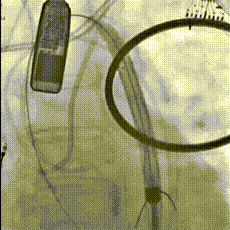

瓣膜释放

可回收功能调整瓣膜深度

瓣膜释放过程

右足位,瓣膜形态,冠脉灌注良好

左头位造影